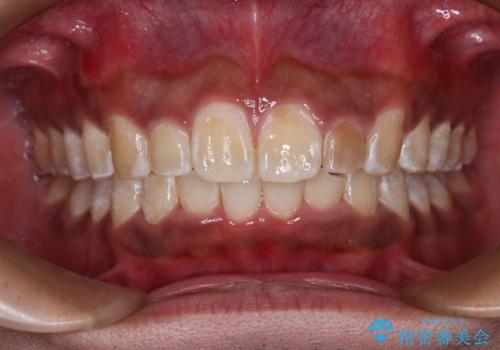

正面や横から見た印象が同じで用であっても、奥歯の咬み合わせが理想的であるかどうかによって、治療の難易度は大きく異なります。

こちらの方も難易度のやや高い状態で、2年以上の期間が予想されましたが、想定通りの2年強で治療を終えることができました。